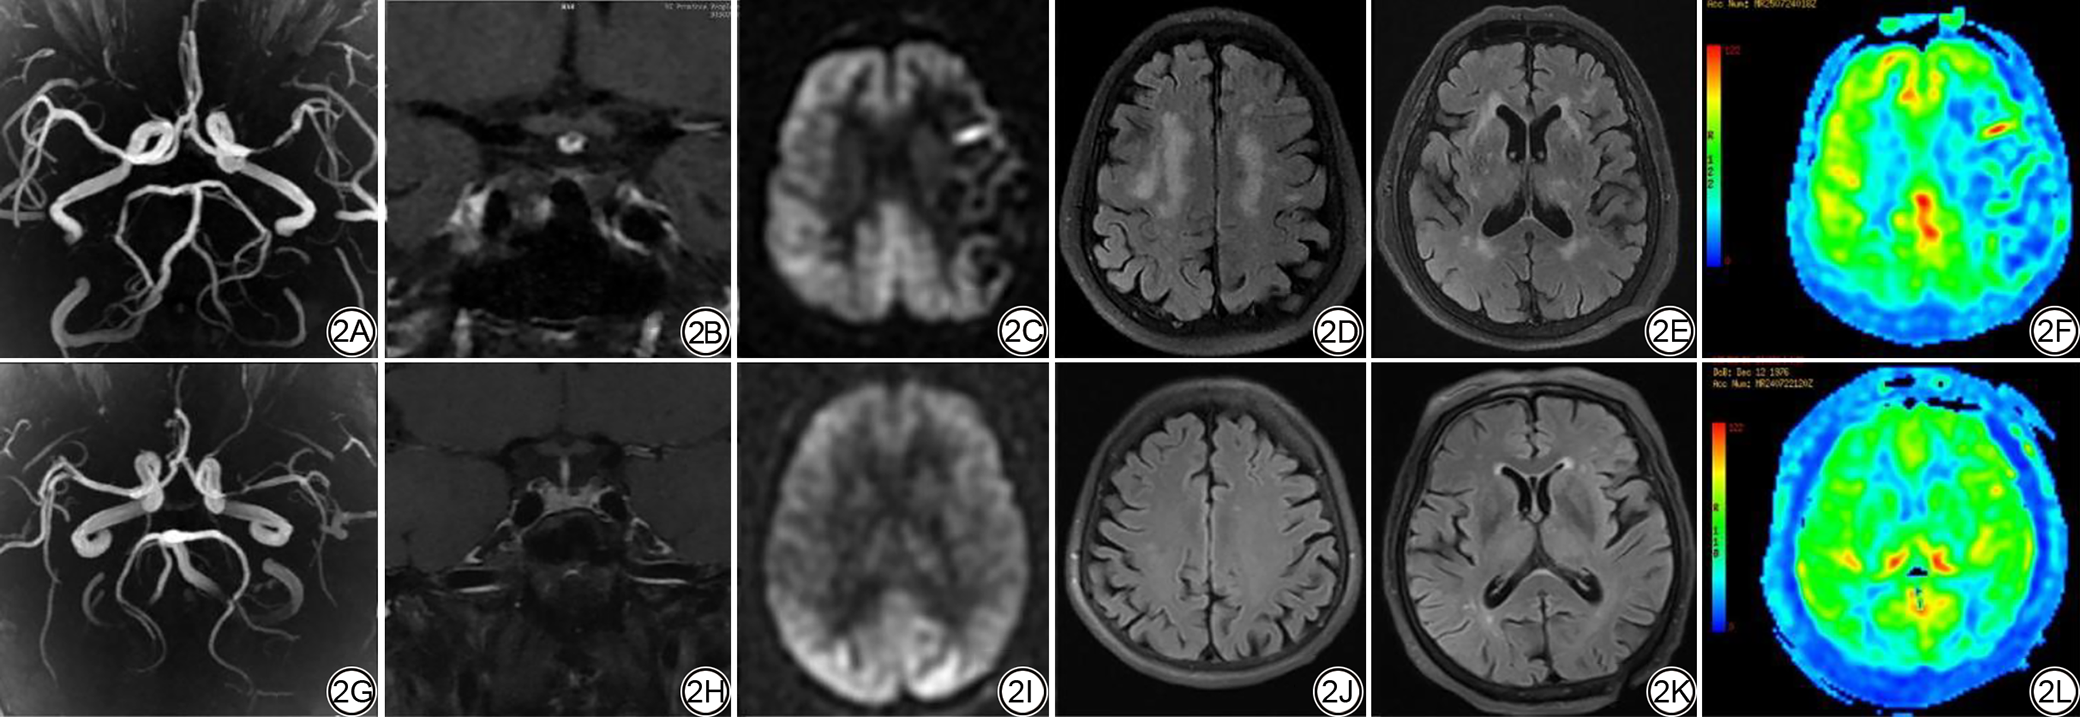

单因素结果显示:性别、总胆固醇、低密度载脂蛋白、血管狭窄程度、总WMH评分、脑深部WMH评分及侧脑室周围WMH评分与侧支循环不良相关。将上述自变量(P<0.05)纳入多因素回归分析模型中,结果显示:血管狭窄程度(P=0.006)、脑深部WMH评分(P=0.008)、脑室周围WMH评分(P=0.017)、总WMH评分(P=0.044)是侧支循环不良的独立危险因素。不同侧支循环状态下ICAS患者的WMH负荷及灌注特征对比图见图2

图2  不同侧支循环状态下ICAS患者的WMH负荷及灌注特征对比图。2A~2F:男,55岁,ICAS患者。2A~2B:MRA-MIP、HR-VWI图,左侧大脑中动脉重度狭窄;2C:3D-pCASL原始图(PLD为2525 ms),侧支循环为1级;2D、2E:轴位Tirm图;WMH评分:脑深部3分;脑室周围3分;总评分6分;2F:灌注伪彩图。2G~2L:女,69岁,ICAS患者。2G、2H:MRA-MIP图、HR-VWI图,左侧大脑中动脉重度狭窄;2I:3D-pCASL原始图(PLD为2525 ms),侧支循环为3级;2J~2K:轴位Tirm图,WMH评分:脑深部1分;脑室周围1分;总评分2分;2L:灌注伪彩图。ICAS:动脉粥样硬化性狭窄;WMH:脑白质高信号;MRA-MIP:磁共振血管造最大密度投影;HR-VWI:高分辨率血管壁成像;3D-pCASL:三维准连续动脉自旋标记;PLD:标记后延迟时间;Tirm:脂肪抑制序列。

Fig. 2  Comparison of WMH burden and perfusion characteristics in ICAS patients with different collateral circulation statuses. 2A-2F: A 55-year-old male patient with ICAS. 2A-2B: MRA-MIP and HR-VWI images showing severe stenosis of the left middle cerebral artery; 2C: 3D-pCASL image (PLD = 2525 ms), collateral circulation is grade 1; 2D-2E: Axial Tirm map; WMH score: 3 points for deep white matter, 3 points for periventricular region, total score is 6 points; 2F: Perfusion color map. 2G-2L: A 69-year-old female patient with ICAS. 2G-2H: MRA-MIP and HR-VWI images showing severe stenosis of the left middle cerebral artery; 2I: 3D-pCASL image (PLD = 2525 ms), collateral circulation is Grade 3; 2J-2K: Axial Tirm map; WMH score: 1 point for deep white matter, 1 point for periventricular region, total score is 2 points; 2L: Perfusion color map. ICAS: intracranial atherosclerotic stenosis; WMH: white matter hyperintensity; HR-VWI: high-resolution magnetic resonance vessel wall imaging; MRA-MIP: magnetic resonance angiography-maximum intensity projection; 3D-pCASL: three-dimensional pseudo-continuous arterial spin labeling; PLD: post labeling delay.